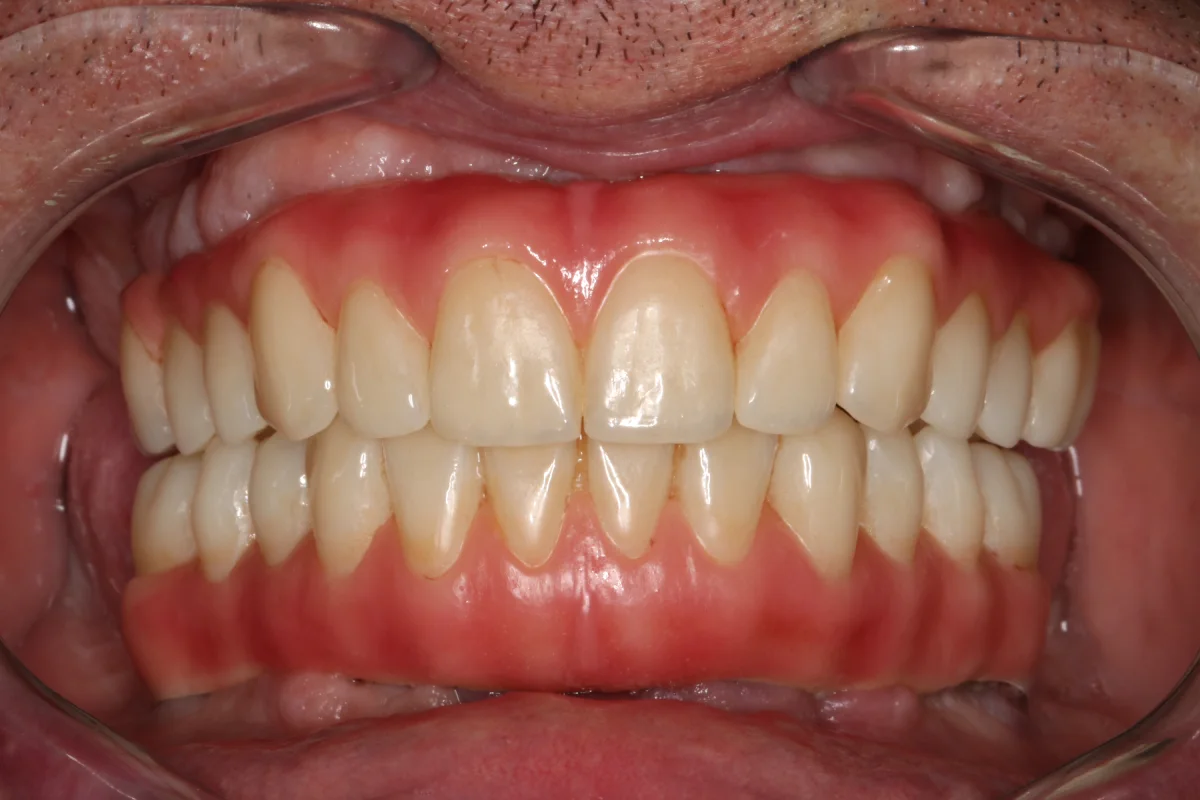

IMPLANTOLOGÍA

Siempre que el paciente reúna los requisitos clínicos adecuados, se irá con unas prótesis provisionales sobre los implantes que se colocarán en esa misma sesión.